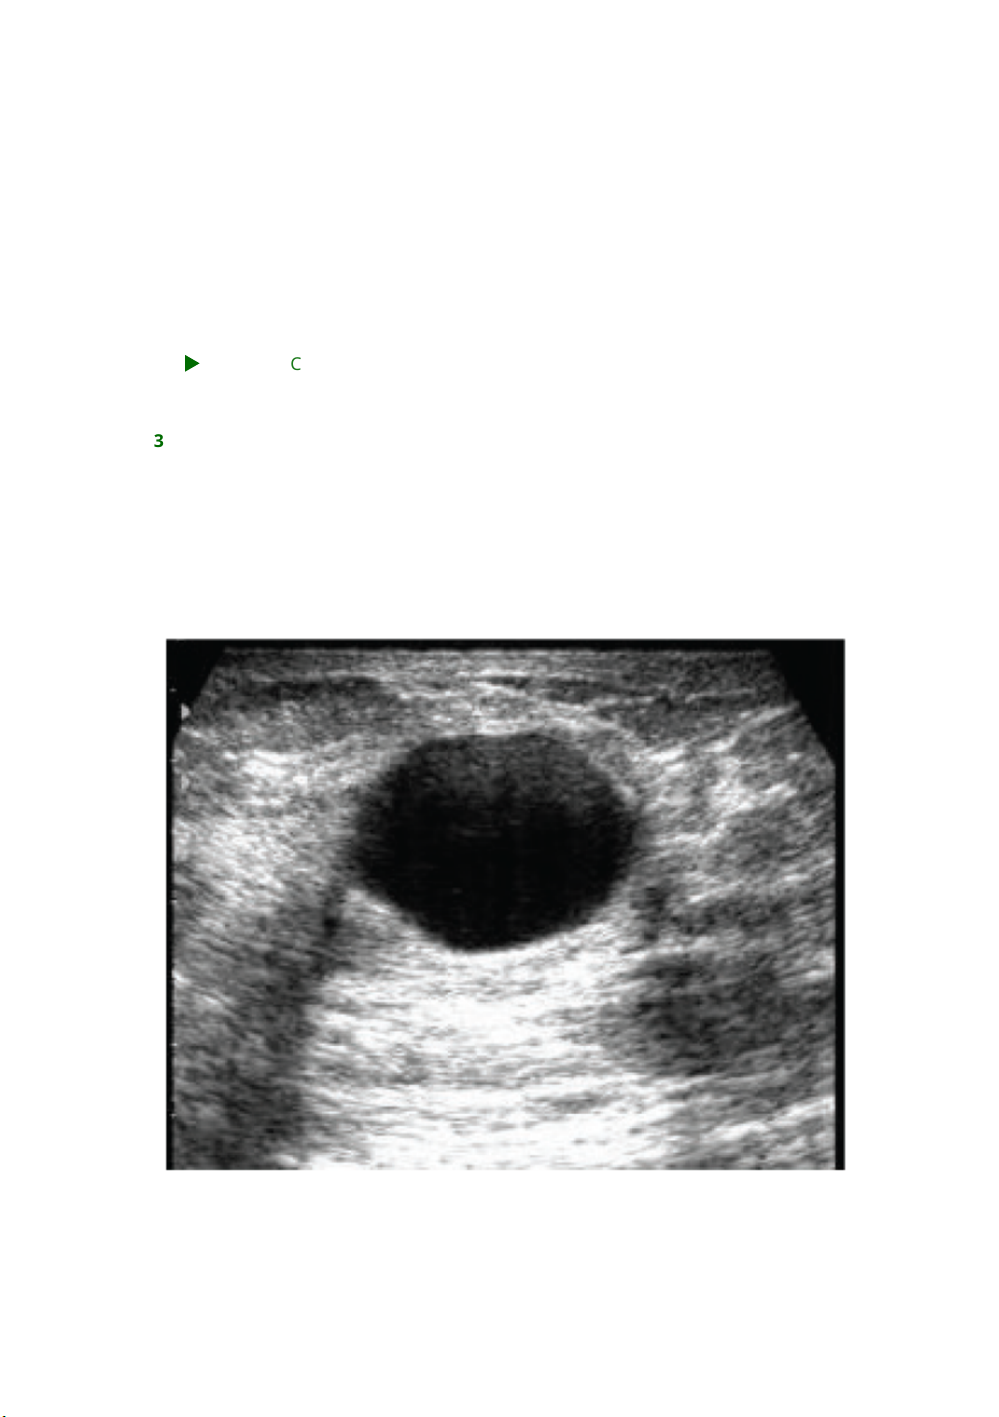

38 (USP – SP – 2018) Paciente de 35 anos de idade refere aparecimento de nódulo

mamário, doloroso, esquerdo, há 1 mês. Neste período, observou pequeno

crescimento do nódulo e dor, com necessidade do uso eventual de anti-

inflamatório não hormonal. Não tem antecedentes mórbidos, pessoais ou

familiares, relevantes. No exame clínico, o nódulo está localizado no quadrante

superolateral esquerdo, tem 3 cm de diâmetro, é móvel e tem limites regulares. O

ultrassom da lesão está mostrado a seguir. Considerando a principal hipótese para

o quadro clínico e imagem apresentada, qual é a melhor conduta para o caso?